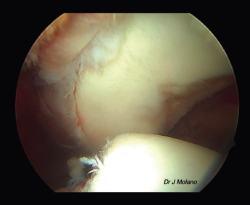

Figura 7. Visión artroscópica desde el portal superior tras anudado de remplissage, implantación intraarticular de la ligamentoplastia y reparación capsulolabral que oculta el ligamento.